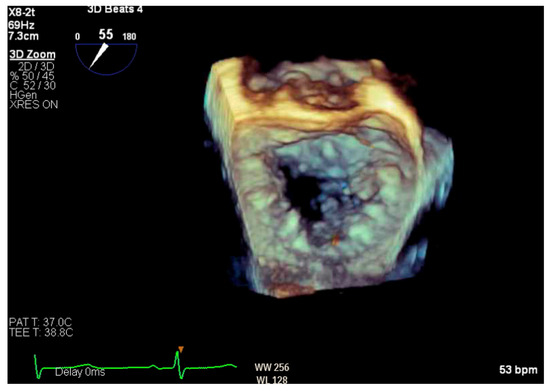

Given the concern for primary MR, a transesophageal echocardiogram (TEE) was performed for further assessment. The study showed prolapse, chordal rupture and partial flail of the A3 leaflet with an area of non-coaptation and severe MR (Figure 6, Supplementary Video S4). Quantification using the proximal isovelocity surface area method revealed an effective orifice area of 0.46 cm2 and a regurgitant volume of 80 milliliters with notable systolic pulmonary vein flow reversal, consistent with severe Carpentier class II MR from prolapse and flail (Figure 7, Supplementary Video S5) [2]. This highlights the role of TEE and 3D imaging in assessing for SAM-independent causes of primary MR in patients with HCM. A TTE alone can miss these anatomical findings, especially in medial (A3 or P3) or lateral (A1 or P1) mitral scallops.

Figure 6.

Three-dimensional reconstruction of mitral valve showing anterior leaflet prolapse and flail.